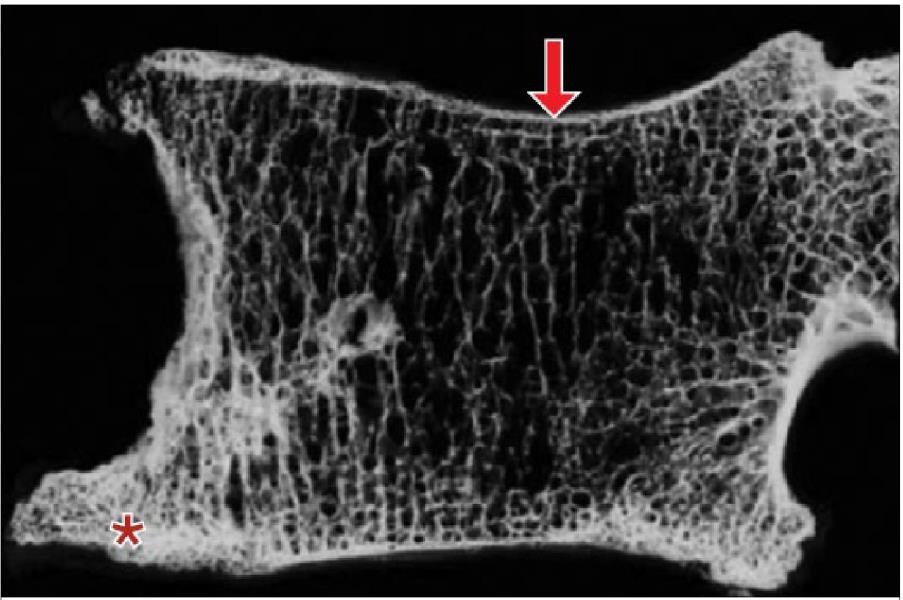

Figure 2. Para-sagittal vertebral body specimen from an elderly patient with noteworthy osteophytes (*), preferential loss of horizontal trabeculae, and pronounced concavity of the upper vertebral body (arrow). These changes drastically reduce the biomechanical load sharing capabilities of the segment. (Adapted from Adams, 2012).

Instrument-assisted adjusting offers several biomechanical advantages in this context, including selectable lower peak forces, minimal preload, and reduced joint excursion. This allows doctors of chiropractic to continue addressing segmental dysfunction and neuromusculoskeletal impairment while respecting fracture risk and tissue tolerance.